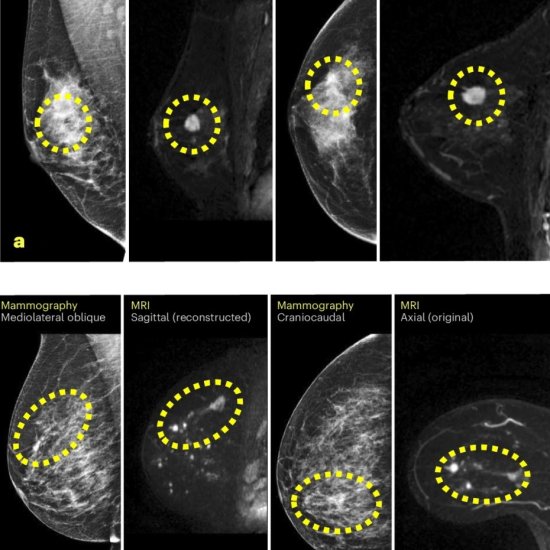

Article • Risk stratification initiatives in Europe and UK

About 60% women in Europe enrolled in a national breast cancer screening programme who have a screening mammogram can feel reasonably confident that radiologists will be able to diagnose early-stage breast cancer. But what about the 30% categorised ... |